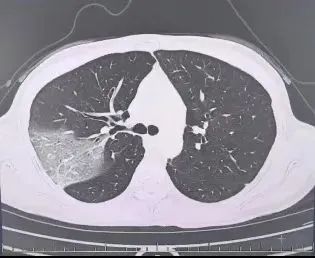

39岁的程女士(假名)是名“责任狂”,在熬夜爆肝责任的同期还保持着极端纤细的身姿。伤风后,她硬扛3天,好几叶肺竟皆出现了“白肺”。

服从情况反而进一步加剧:好几叶肺皆出现了“白肺”阵势,指间血氧填塞度唯有88%,血心肌酶谱、肌钙卵白的主义、肝功能的主义也出现了说明的极端。